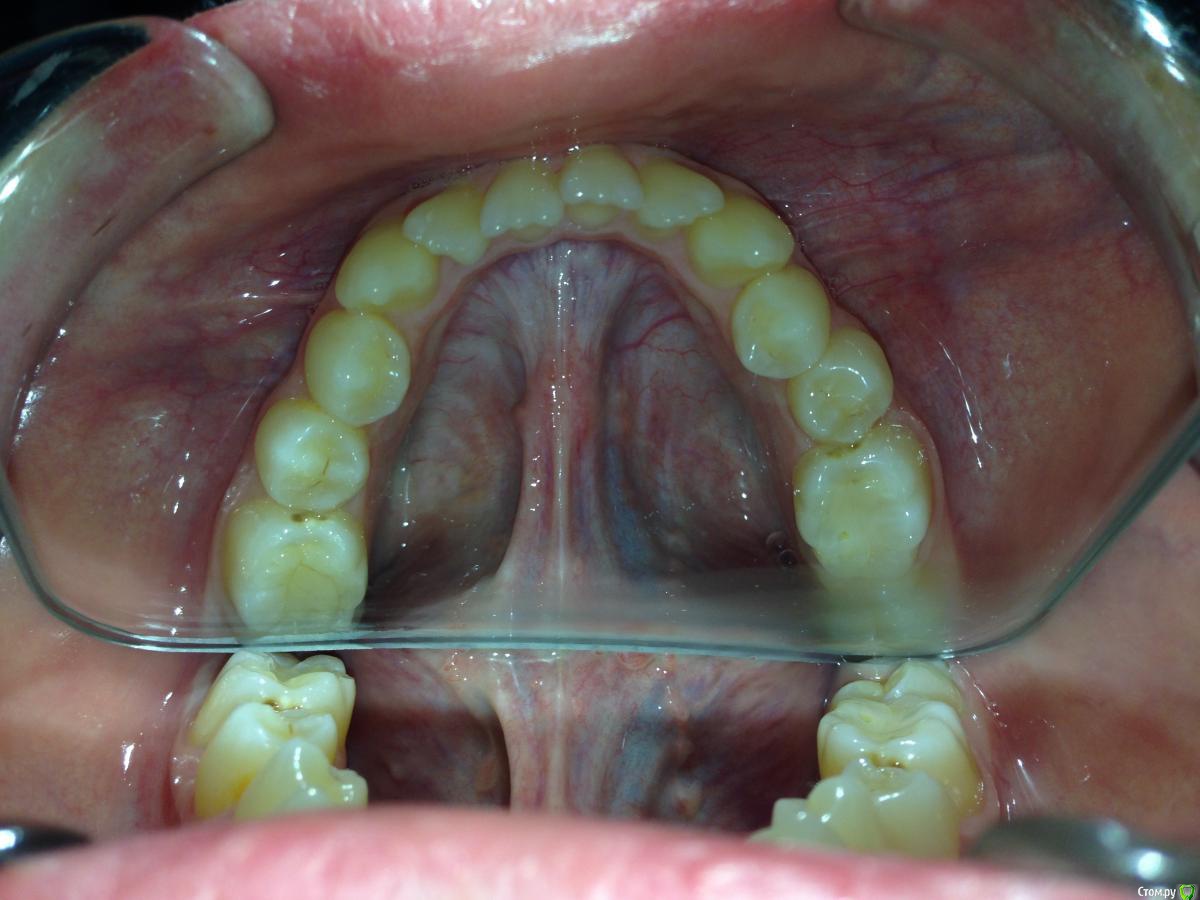

Алевтина Петровна Опубликовано 26 августа, 2015 Поделиться Опубликовано 26 августа, 2015 Всем добрый вечер. Я начинающий ортодонт. Надеюсь,что вы поможете с планом лечения. Пришел пациент. 13 лет. Ситуация по мне непростая, но очень интересная. Ссылка на комментарий

Алевтина Петровна Опубликовано 26 августа, 2015 Автор Поделиться Опубликовано 26 августа, 2015 Прикрепляю дополнительные фото, извините за качество. Это моя первая публикация, пытаюсь разобраться. Ссылка на комментарий

Yana guapa Опубликовано 26 августа, 2015 Поделиться Опубликовано 26 августа, 2015 как только прорежутся нижние 7-ки, я бы сразу послала бы на удаление зачатков нижних 8-ок. аппарат RPE конечно можно поставить. но 13 лет - критический возраст. стоит вопрос о необходимости SARPE. иначе можем получить результат только на уровне зубов (просто их наклонт будет). а Если хотим реально челюсть расширить, то лучше вместе с хирургом. И по срокам быстрее , и результативнее и стабильнее. 1 Ссылка на комментарий

Molox Опубликовано 27 августа, 2015 Поделиться Опубликовано 27 августа, 2015 Имхо, но раз апексы 5-к еще не сформировались, можно расчитывать на скелетный эффект. Ссылка на комментарий